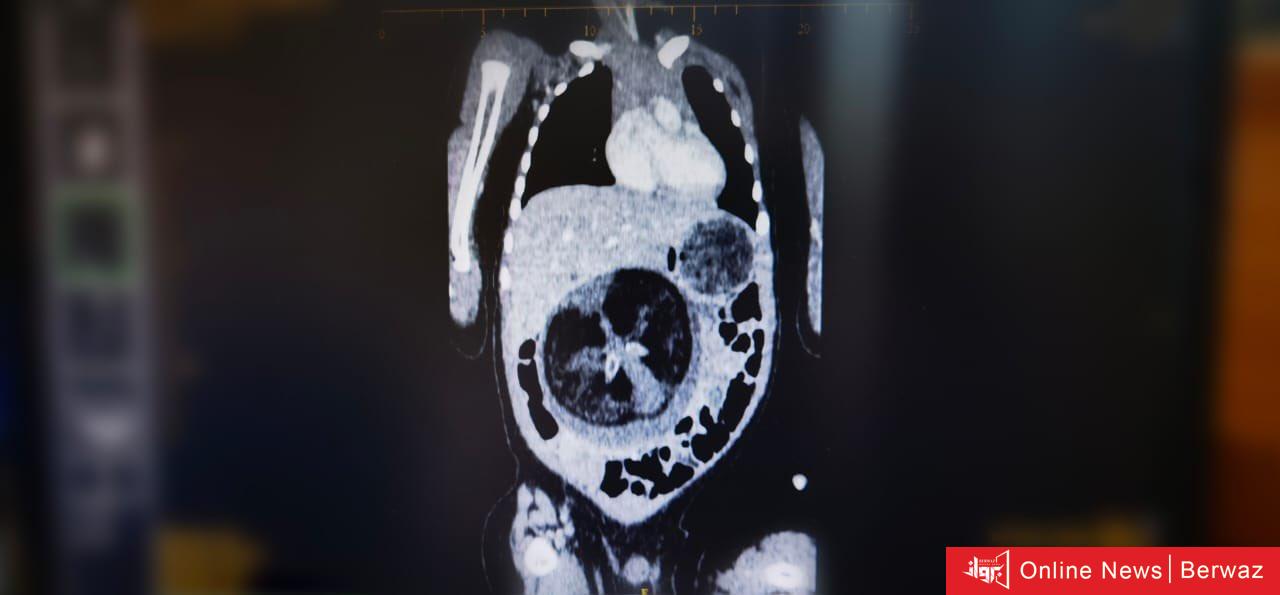

تمكن قسم جراحة الأطفال بالمستشفى السلطاني في سلطنة عمان من إجراء عملية جراحية نادرة تمثلت في استئصال جنين من داخل جنين لطفل يبلغ من العمر ثمانية أشهر، وتعد تلك الحالة نادرة الحدوث عالميًا

وتعرف هذه الظاهرة الطبية بـ Fetus in Feto، وتحدث بنسبة 1 بين كل 500 ألف حالة ولادة حية على مستوى العالم.